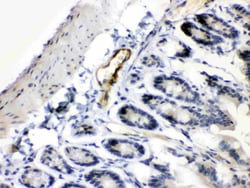

Reconstitute with 0.2 mL of distilled water to yield a concentration of 500 μg/mL. Positive Control - WB: rat stomach tissue, mouse ovary tissue. IHC: mouse intestine tissue, rat intestine tissue, rat cardiac muscle tissue, human intetsinal cancer tissue.

| Immunohistochemistry (Paraffin), Western Blot | |